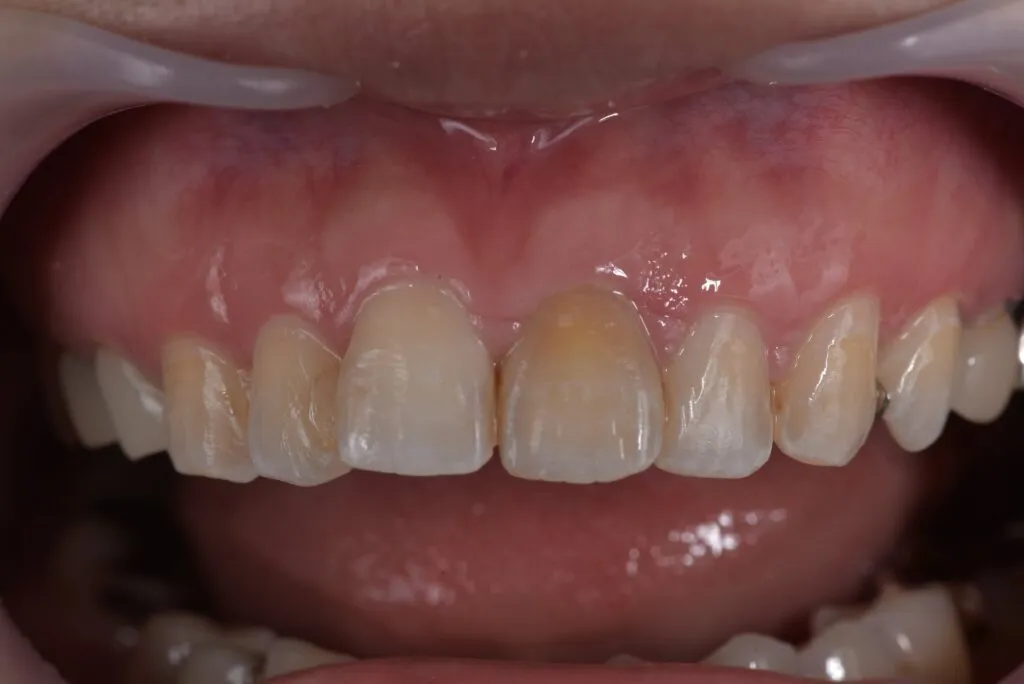

case2

Before

After

治療内容 | 口腔内診査〜カウンセリング 歯周初期治療 仮歯を入れ機能的な評価 最終的な型取り〜装着 |

---|---|

治療期間 | 1ヶ月〜2ヶ月 |

治療回数 | 5回 |

リスク | クリーニングにこない場合噛み合わせの確認ができないため装着していった人工物が割れてしまう可能性があるため、今後のメンテナンスが必須となる |

費用(税込) | 約¥143,000 |